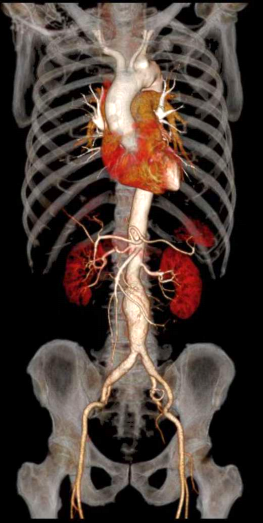

Công nghệ DE tiên tiến: Tích hợp đa dạng kỹ thuật năng lượng kép, hình ảnh rõ nét

Phân tích toàn diện: Cung cấp đồng thời đánh giá định tính và định lượng chuyên sâu.

Giá trị lâm sàng vượt trội: Hỗ trợ nâng cao độ tin cậy trong chẩn đoán và điều trị.

Hình ảnh lâm sàng